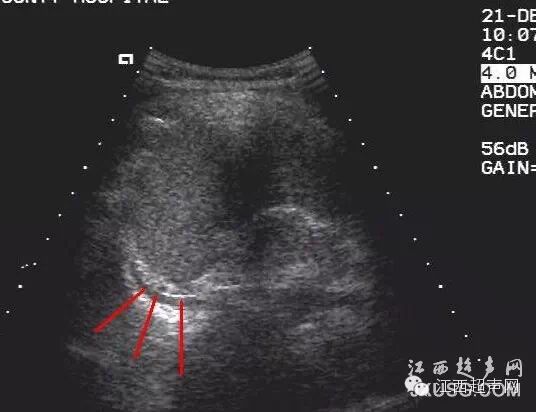

55.患者女,因左侧腰背部疼痛到我院门诊就诊,当时泌尿科考虑为泌尿系结石就申请B超检查:

而且前一段时间CT室的人和我们说,我们超声诊断的肝内多发性囊肿在CT增强时部分囊性占位内可见增强剂充盈,这件事也给我们提示不要老是习惯性思维,要考虑全面点,同时多运用CDFI。